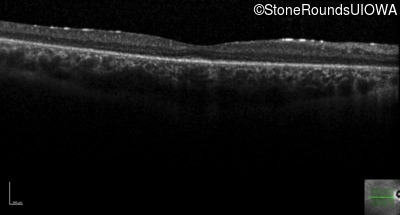

Optical Coherence Tomography - Right - 20/30 -2

Exemplar / OCT Stack